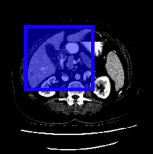

Consider a three-dimensional object within a volume. It is straightforward to produce a 3D bounding box of the object by finding its extreme points in the three coordinate axes. While this 3D bounding box will be tight in the 3D sense, its rectangular cross-sections will not, in general, remain tight with respect to the planar cross-sections of the volume. Fig. 1 illustrates such a case for the task of liver segmentation in a CT volume. In the Experiments section we show that the success of existing 2D weakly-supervised segmentation methods relies on the bounding boxes being tight and therefore the tightness of the individual 2D bounding boxes should be corrected before training and applying a segmentation CNN.

(a)

(b)

(c)

(d)